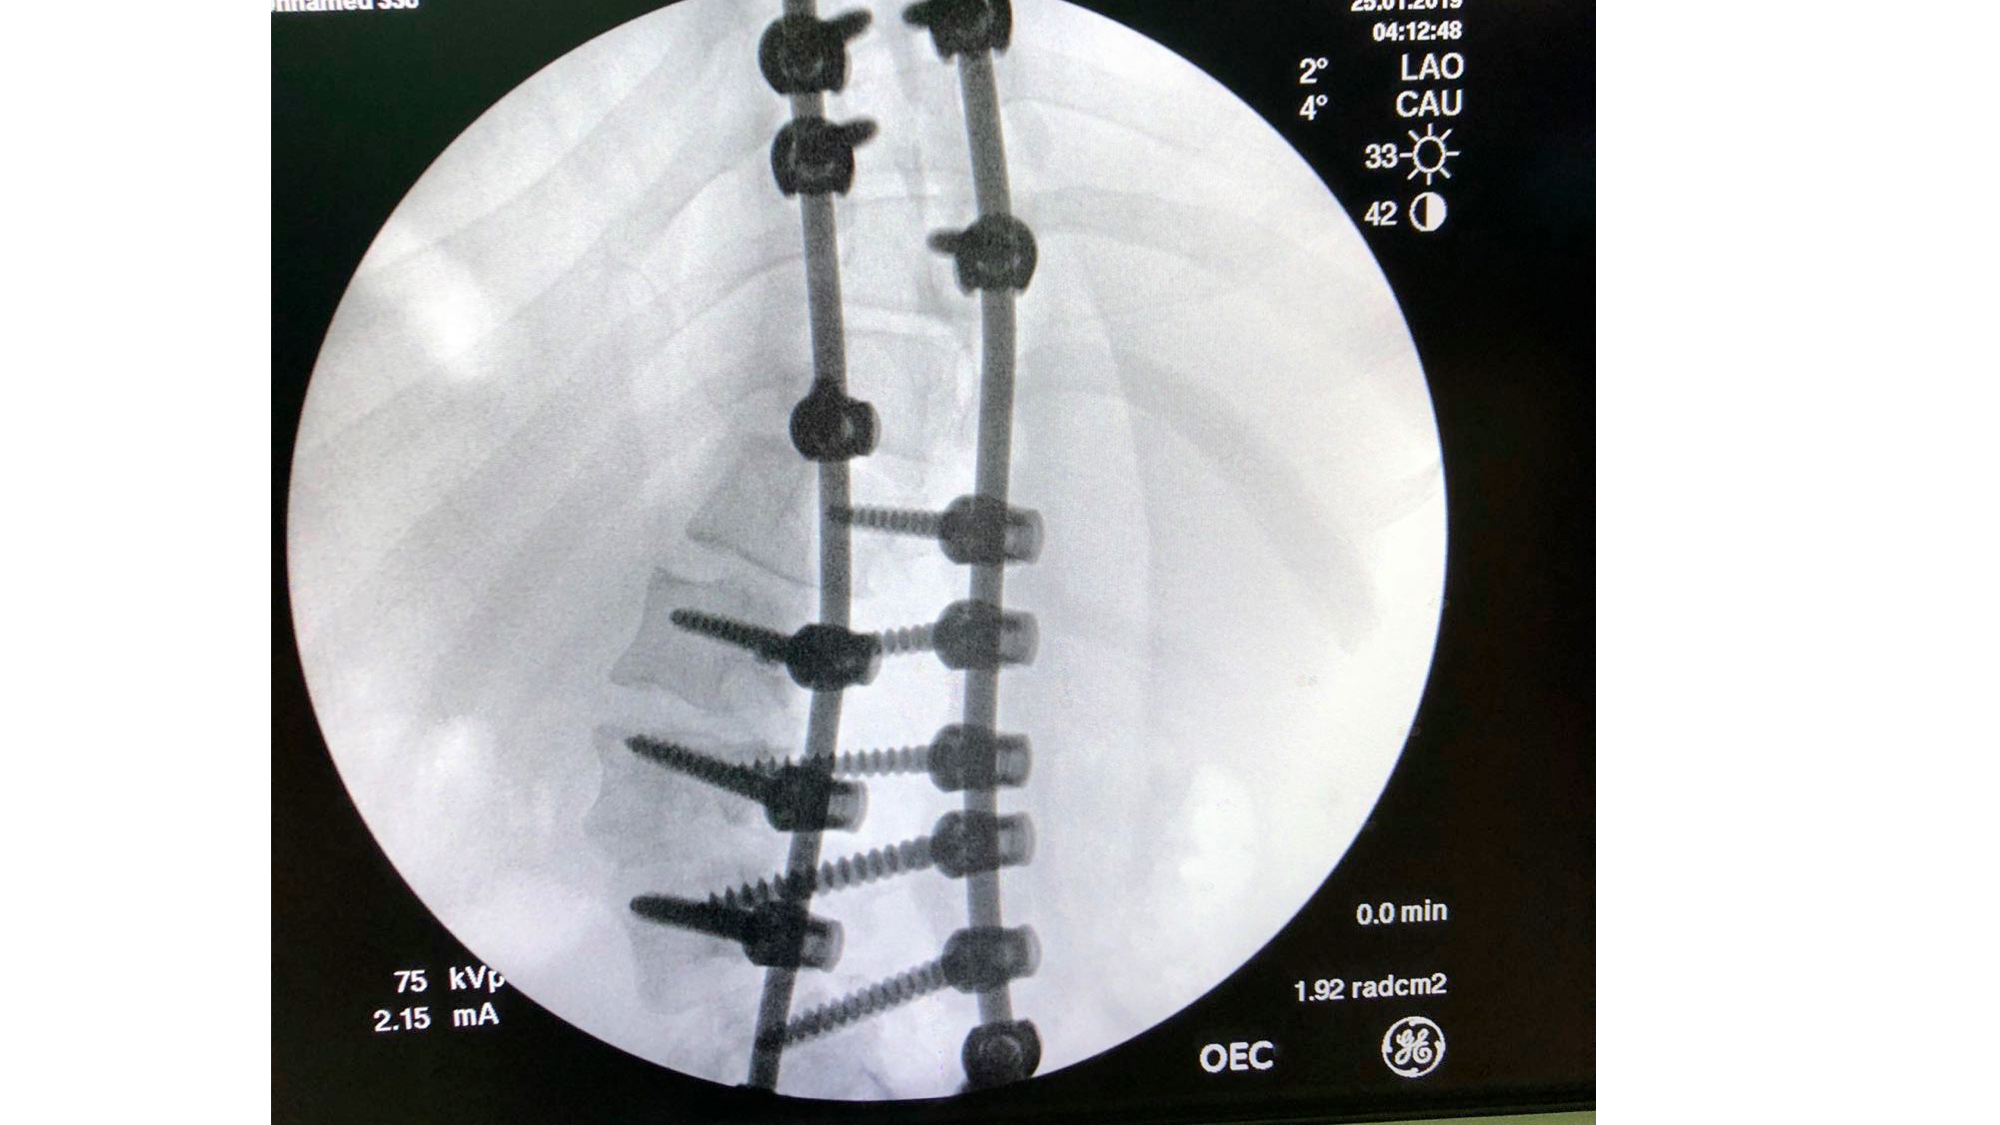

I was also able to meet the first two spine surgery fellows at AaBET. They are both neurosurgeons. The plan after next year is to alternate orthopedic with neurosurgery spine fellows. In addition to their teaching at AaBET, they are mentored by Dr Fasil Mesfin of Univeristy of Missouri, with whom they have weekly cases conferences. They were excited to show me two massive spine tumors they just operated on, one a giant, dumbbell shaped neurofibroma of the lower thoracic spine with bone involvement and preoperative paraparesis; the other a huge aneurysmal bone cyst of posterior lumbar element. Both needed pedicle screw instrumentation and big exposures. I am not a spine surgeon but the operative photos and postop xrays were very impressive.